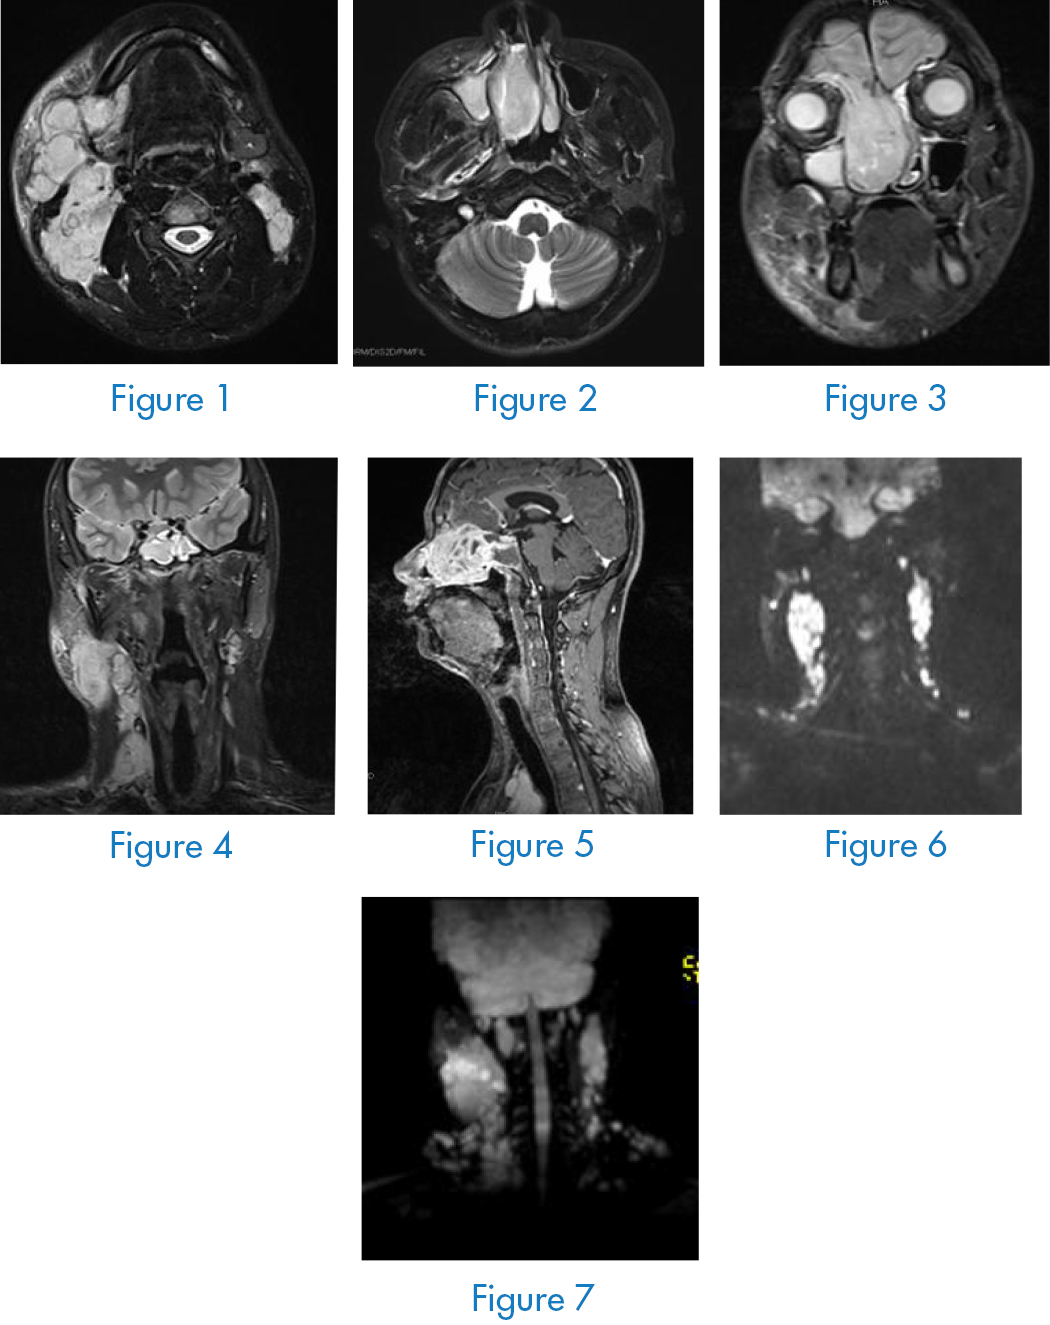

Nasopharyngeal neck enhancement MRI (Figure 1–7): the right nasal cavity involves abnormal signal masses of the ethmoid sinus, maxillary sinus, and frontal sinus and is significantly unevenly strengthened, which is consistent with the performance of embryonal rhabdomyosarcoma, and the bone of the inner side wall of the right maxillary sinus Damage, right frontal base may be involved, multiple lymph node metastases in the right pharyngeal side, submandibular area, bilateral deep neck, carotid sheath area, right frontal sinus, sphenoid sinus, and maxillary sinus with effusion. Head MRI, thoracoabdominal CT No abnormalities were found in bone scans. A new biopsy of the right nasal cavity was performed, and the pathological diagnosis was: (right nasal cavity) embryonic rhabdomyosarcoma. Immunohistochemistry: Final diagnosis: right nasal embryonic rhabdomyosarcoma phase III [3].